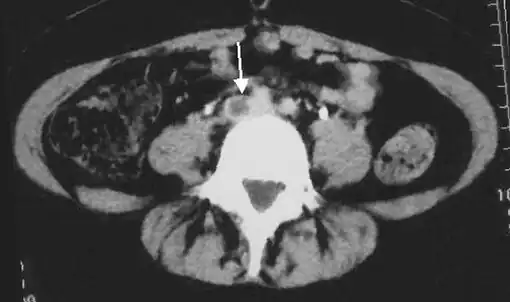

An abdominal CT scan demonstrating an iliofemoral DVT, with the clot in the right common iliac vein of the pelvis